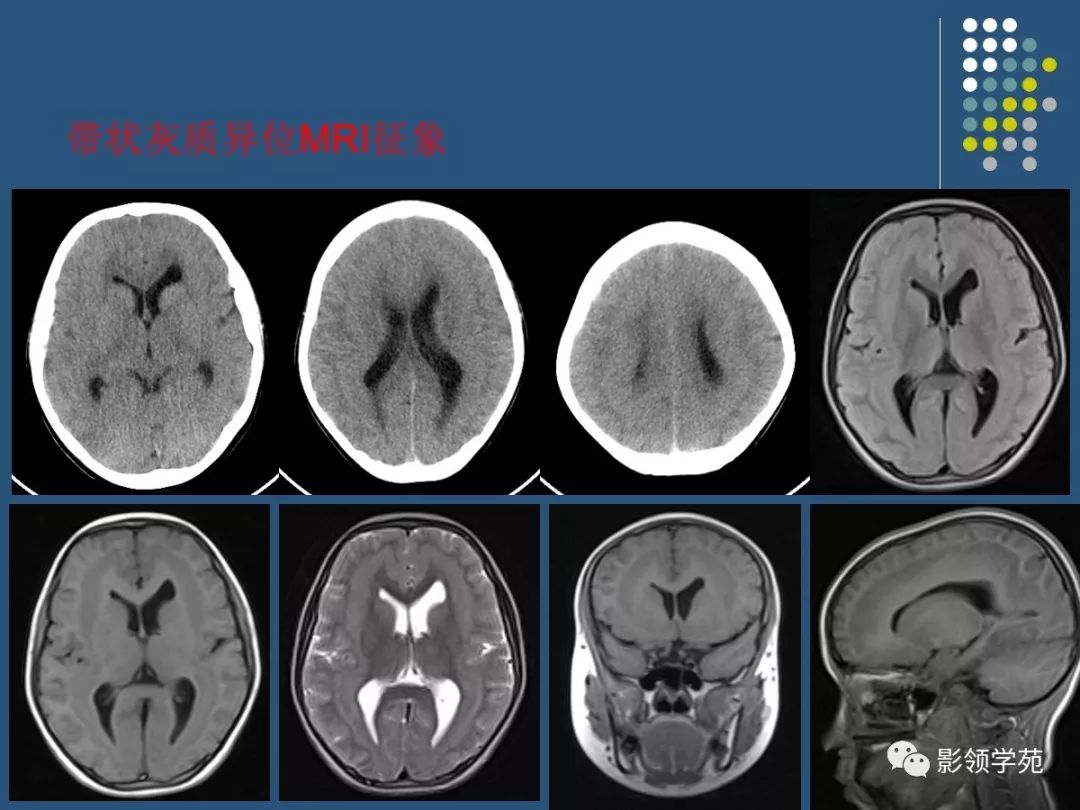

脑灰质异位ct图片

脑灰质异位ct图片,脑白质和脑灰质ct图片

脑灰质异位

精品课件脑灰质异位症的影像诊断

鉴别诊断:孤立性灰质异位应与颅内占位鉴别.

灰质异位